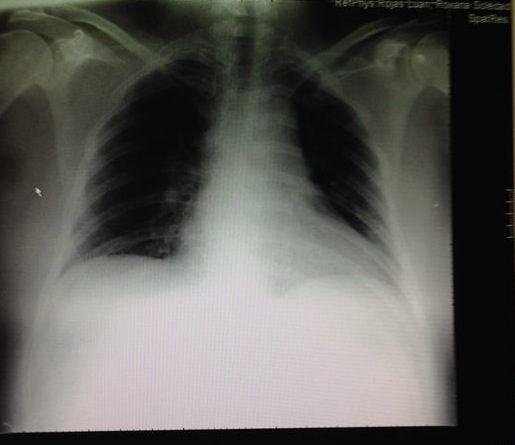

The white blood cell count was 16360cells/mm 3 with 13740 neutrophils and haemoglobin level was 10.2g/dL. Platelet count189/μL. No abnormalities were detected on chest radiography (Figure 1). A lumbar puncture was performed and purulent cerebrospinal fluid was collected with pleiocytosis, hypoglicorrachia and hyperproteinorrachia. The Gram-stained and pneumococcal antigen in urine were either negative. A computed tomography scan of the brain was unremarkable. Suspecting postreservoir refill related meningitis, empirical treatment with vancomicine and meropenem was promptly initiated and her overall status improved. On the third day of admission her cardiac auscultation detected an holodiastolic murmur at the left upper sternal border as well as bilateral crackles. A new chest x-ray showed alveolar opacity in the left lower lobe (Figure 2).

Figure 1 Chest X-ray on admission.

Figure 2 Chest x-ray on the third day of admission showed alveolar opacity in the left lower lobe.